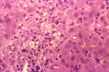

Cholate stasis

Fig 52 - CHOLATE STASIS: The periportal hepatocytes are swollen, hydropic and foamy, pseudoxanthomatous cells. These are the changes of so-called "biliary piece meal necrosis" that occurs in stagnation of bile flow. The changes are attributed to retention of bile acids. This sample is from a case of primary biliary cirrhosis (PBC).